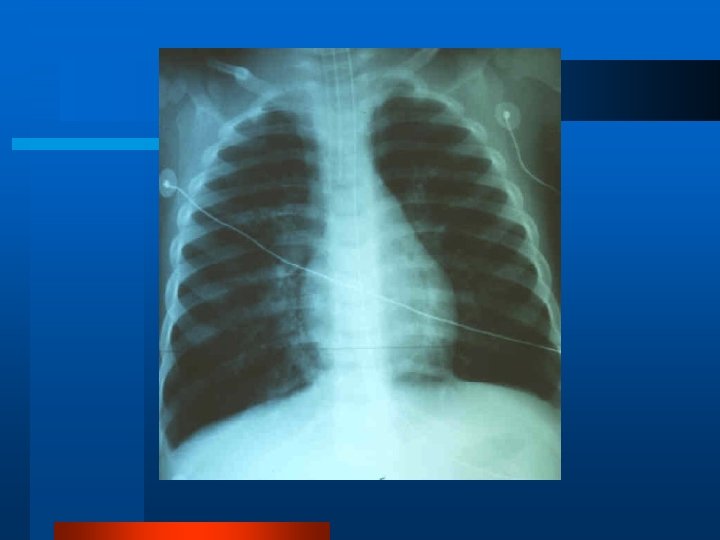

CT thorax ARDS Normal